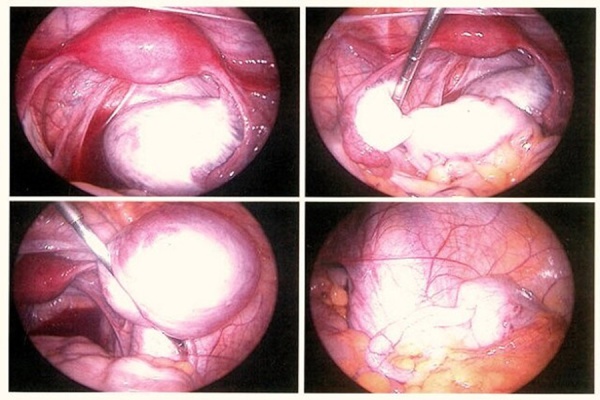

ЩҫШ§ШҜЩ…ЩҮШұ Ш§ЩҒШІЩҲШҜ: ЫҢЪ©ЫҢ Ш§ШІ ЩҲЫҢЪҳЪҜЫҢвҖҢЩҮШ§ЫҢ Ш®Ш§Шө Ш§ЫҢЩҶ Ъ©ЩҶЪҜШұЩҮШҢ ШЁШұЪҜШІШ§ШұЫҢ Ш¬ШұШ§ШӯЫҢ ШІЩҶШҜЩҮ Ш§ШіШӘ Ъ©ЩҮ ШЁШұШ§ЫҢ Ш¬ШұШ§ШӯШ§ЩҶ ШҜШұ ШіШұШ§ШіШұ ШҜЩҶЫҢШ§ ЫҢЪ© ЪҶШ§Щ„Шҙ Щ…ШӯШіЩҲШЁ Щ…ЫҢвҖҢШҙЩҲШҜ. Щ…Ш§ ШЁШ§ ЩҮЩ…Ъ©Ш§ШұЫҢ Щ…ШұЪ©ШІ ЩҶШ§ШЁШ§ШұЩҲШұЫҢ Ш§ШЁЩҶ ШіЫҢЩҶШ§ ЩҲ ЩҫЪҳЩҲЩҮШҙЪҜШ§ЩҮ ШіЫҢЩҶШ§ШҢ ШӘЩҲШ§ЩҶШіШӘЩҮвҖҢШ§ЫҢЩ… Ш§ШІ Ш¬ШҜЫҢШҜШӘШұЫҢЩҶ ШӘШ¬ЩҮЫҢШІШ§ШӘ Щ„Ш§ЩҫШ§ШұШ§ШіЪ©ЩҲЩҫЫҢ ЩҲ Ш¬ШұШ§ШӯЫҢ Щ…ЫҢЩҶЫҢЩ…Ш§Щ„ЫҢ Ш§ЫҢЩҶЩҲЫҢШІЫҢЩҲ ШЁШұШ§ЫҢ ШҜШұЩ…Ш§ЩҶ ШЁЫҢЩ…Ш§ШұШ§ЩҶ ШўЩҶШҜЩҲЩ…ШӘШұЫҢЩҲШІ Ш§ШіШӘЩҒШ§ШҜЩҮ Ъ©ЩҶЫҢЩ…. ШҜШұ Ш§ЫҢЩҶ Ъ©ЩҶЪҜШұЩҮШҢ Ш¬ШұШ§ШӯЫҢ ШІЩҶШҜЩҮвҖҢШ§ЫҢ ШЁШ§ ШӯШ¶ЩҲШұ ШҜЪ©ШӘШұ ШұШЁЫҢШ№ЫҢШҢ Ш¬ШұШ§Шӯ Щ…ЫҢЩҶЫҢЩ…Ш§Щ„ЫҢ Ш§ЫҢЩҶЩҲЫҢШІЫҢЩҲ Ш§ШІ Ъ©ШҙЩҲШұ Ш№ШұШ§ЩӮШҢ ШЁШұЪҜШІШ§Шұ Ш®ЩҲШ§ЩҮШҜ ШҙШҜ. Ш§ЫҢЩҶ Ш¬ШұШ§ШӯЫҢ ШЁЩҮ ШұЩҲШҙ Щ„Ш§ЩҫШ§ШұШ§ШіЪ©ЩҲЩҫЫҢ Ш§ЩҶШ¬Ш§Щ… Щ…ЫҢвҖҢШҙЩҲШҜШҢ ЪҶШұШ§ Ъ©ЩҮ Щ…ШӘШЈШіЩҒШ§ЩҶЩҮ ШЁЩҮ ШҜЩ„ЫҢЩ„ ШӘШӯШұЫҢЩ…вҖҢЩҮШ§ШҢ ЩҮЩҶЩҲШІ Ш§Щ…Ъ©Ш§ЩҶ Ш§ШіШӘЩҒШ§ШҜЩҮ Ш§ШІ ШіЫҢШіШӘЩ…вҖҢЩҮШ§ЫҢ ШұШЁШ§ШӘЫҢЪ© ШҜШұ Ш§ЫҢШұШ§ЩҶ ЩҲШ¬ЩҲШҜ ЩҶШҜШ§ШұШҜ. Ш§Щ…ЫҢШҜЩҲШ§ШұЫҢЩ… Ъ©ЩҮ ШЁЩҮвҖҢШІЩҲШҜЫҢ ШЁШ§ Ъ©Щ…Ъ© ШҙШұЪ©ШӘвҖҢЩҮШ§ЫҢ ШҜШ§ЩҶШҙвҖҢШЁЩҶЫҢШ§ЩҶ ШҜШ§Ш®Щ„ЫҢШҢ Ш§ЫҢЩҶ ЩҒЩҶШ§ЩҲШұЫҢвҖҢЩҮШ§ ШҜШұ Ъ©ШҙЩҲШұ ШӘЩҲЩ„ЫҢШҜ ЩҲ ШҜШұ ШҜШұЩ…Ш§ЩҶ ШўЩҶШҜЩҲЩ…ШӘШұЫҢЩҲШІ Щ…ЩҲШұШҜ Ш§ШіШӘЩҒШ§ШҜЩҮ ЩӮШұШ§Шұ ЪҜЫҢШұЩҶШҜ.